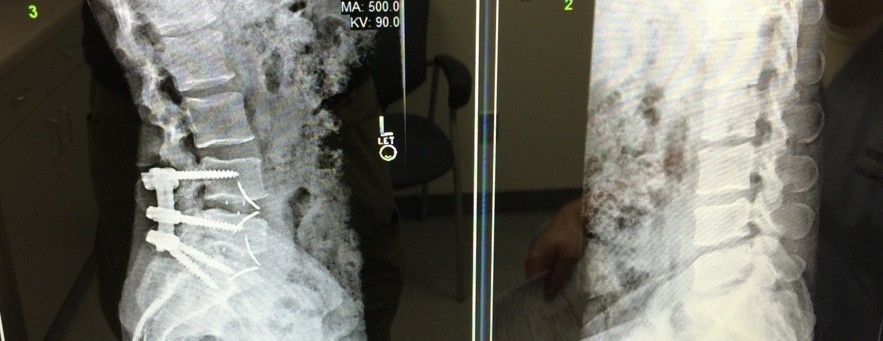

HOLY CRAP DUDE.......YOU GOT SCREWED!Here's my new titanium hardware. Should I compare it to the material that it replaced?

View attachment 135538View attachment 135539View attachment 135540